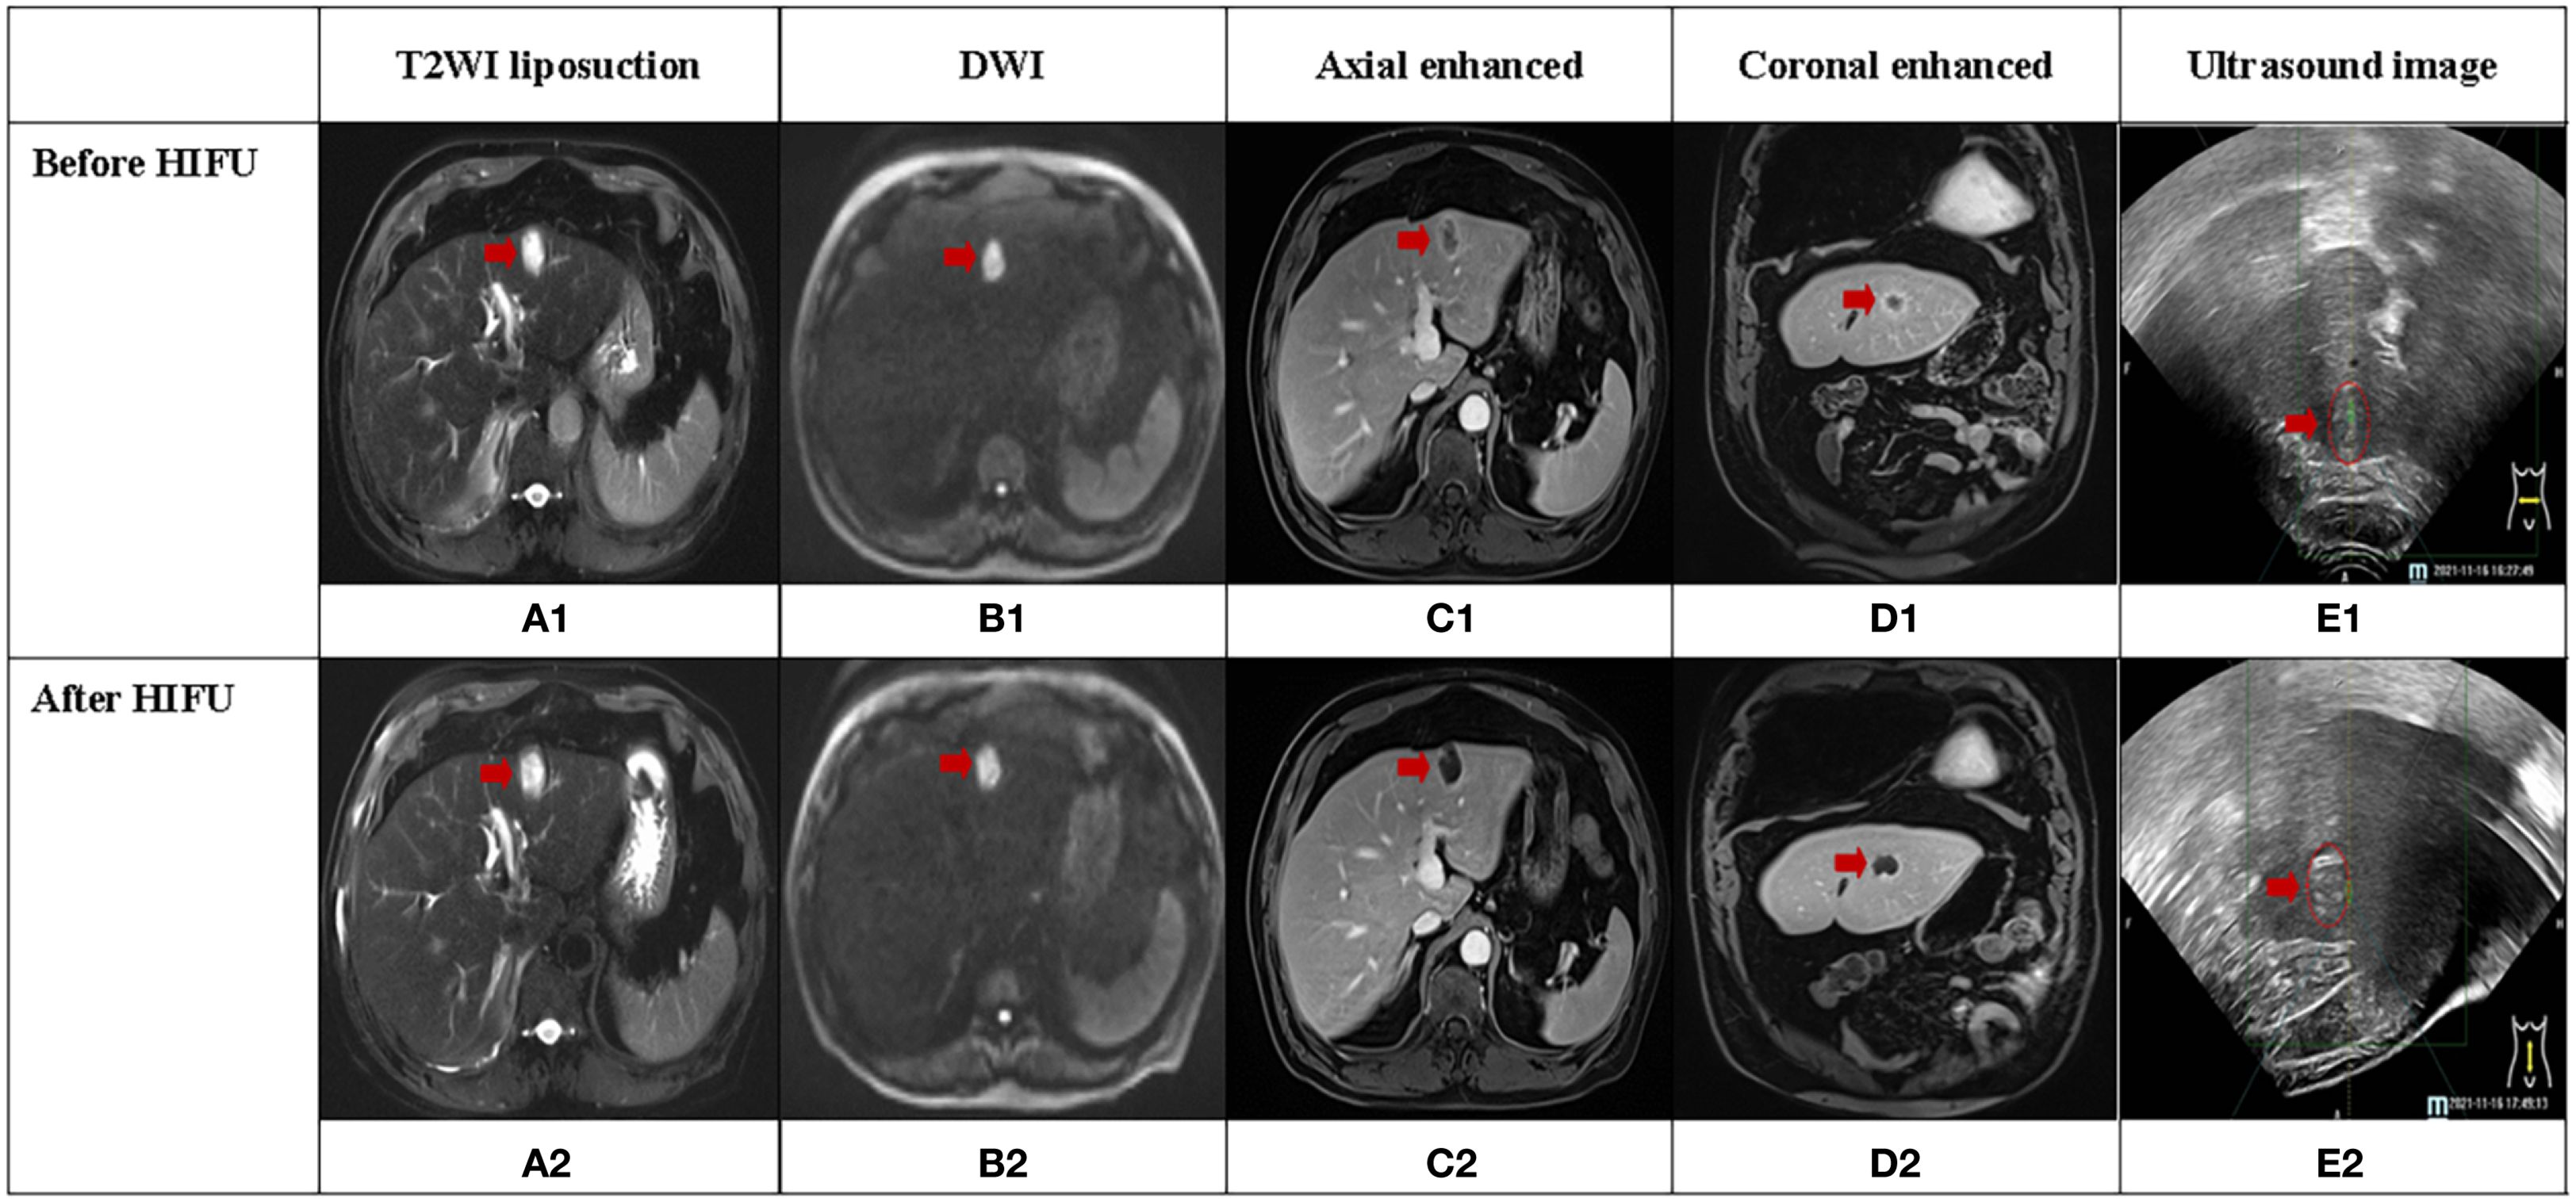

In the Combined HIFU group, there were 12 male and 11 female patients with a median age of 63 years. In the Only HIFU group, there were 19 male and 6 female patients with a median age of 60 years. With respect to the type of liver cancer, each group included 9 cases of primary liver cancer and 16 cases of secondary liver cancer. Among the primary liver cancer cases, two-thirds were at stage III and one-third at stage IV; all secondary liver cancer cases were at stage IV. No patients in either group had Child-Pugh class C liver function. There were no statistically significant differences in baseline characteristics between the two groups (p>0.05), indicating that they were comparable. In the Combined HIFU group, the mean number of cycles of antiangiogenic targeted therapy administered prior to HIFU treatment was 4.5 (range:1–11). Specifically, 60% of the patients received bevacizumab, 24% lenvatinib, 12% anlotinib, and 4% fruquintinib (Table 1). HIFU treatment parameters of the two groups are presented in Table 2. During HIFU treatment, changes in ultrasound grayscale images can reflect real-time treatment efficacy, corresponding to the degree of coagulated necrosis in target lesions (5–7). As illustrated in Figure 1, the intraoperative ultrasound image displayed significant alterations in grayscale in a lesion in the left lobe of the liver after HIFU treatment, with the echo intensity being significantly higher than the initial treatment image. In the current study, the median grayscale occurrence time was 25s in the Combined HIFU group and 104s in the Only HIFU group, and the difference was statistically different (z=-2.00, p=0.04). This finding suggests that the combination treatment achieved faster and more sensitive treatment responses. Under the guidance of a senior radiologist, CE-MRI images were analyzed, and changes in lesions before and after HIFU treatment were compared, measuring lesion size and coagulated necrosis area to determine treatment efficacy according to mRECIST1.1. 60% (15/25) of patients in the Combined HIFU group had a higher degree of coagulative necrosis compared to the Only HIFU group, and the 1-month disease control rate (DCR) was 96% and 84%, respectively. Despite some lesions not displaying evidence of coagulative necrosis, follow-up revealed that they benefited from HIFU treatment in controlling short-term lesion progression, and the likelihood of local lesion progression after treatment was only 1/4 of compared to the control group (Figure 2, Table 3). Furthermore, this study also demonstrated that the efficacy of HIFU therapy varied across different subtypes of advanced carcinoma. Both the coagulative necrosis rate and DCR were higher in patients with primary liver cancer than in those with secondary liver cancer, with this difference being more pronounced in the combined therapy group (Table 3). However, due to the small sample size of each subgroup, statistical analysis could not be performed. Therefore, studies with a larger sample size will be required to further validate this finding.

Figure 1. A case of secondary liver cancer achieved complete response (CR) after HIFU treatment, and the lesion was located in the left lobe of the liver (red arrow). (A1-D1, A2-D2) illustrate MRI sequences before and after HIFU treatment, respectively. (E1, E2) display ultrasound images before and after HIFU treatment, respectively. (E2) depicts significant grayscale changes in the lesion.

Figure 1 depicts CE-MRI and intraoperative ultrasound images of a CR secondary liver cancer before and after HIFU treatment. The lesion was located in the left outer lobe of the liver and measured approximately 3cm×2cm. Pre-treatment revealed a low signal on T1WI, a high signal on T2WI, a high signal on DWI, and uneven enhancement on contrast-enhanced scan, predominantly with marginal ring enhancement. Post-treatment imaging showed a low signal on T1WI, a high signal on T2WI, and a high signal on DWI. There was no evidence of enhancement areas on enhanced scan, only marginal linear enhancement. Before and after treatment, coagulative necrosis (non-enhanced area) completely covered the original lesion. Ultrasound images displayed hyperechoic grayscale change (hyperechoic region) after treatment, which was consistent with the coagulated necrosis area observed on CE-MRI images.